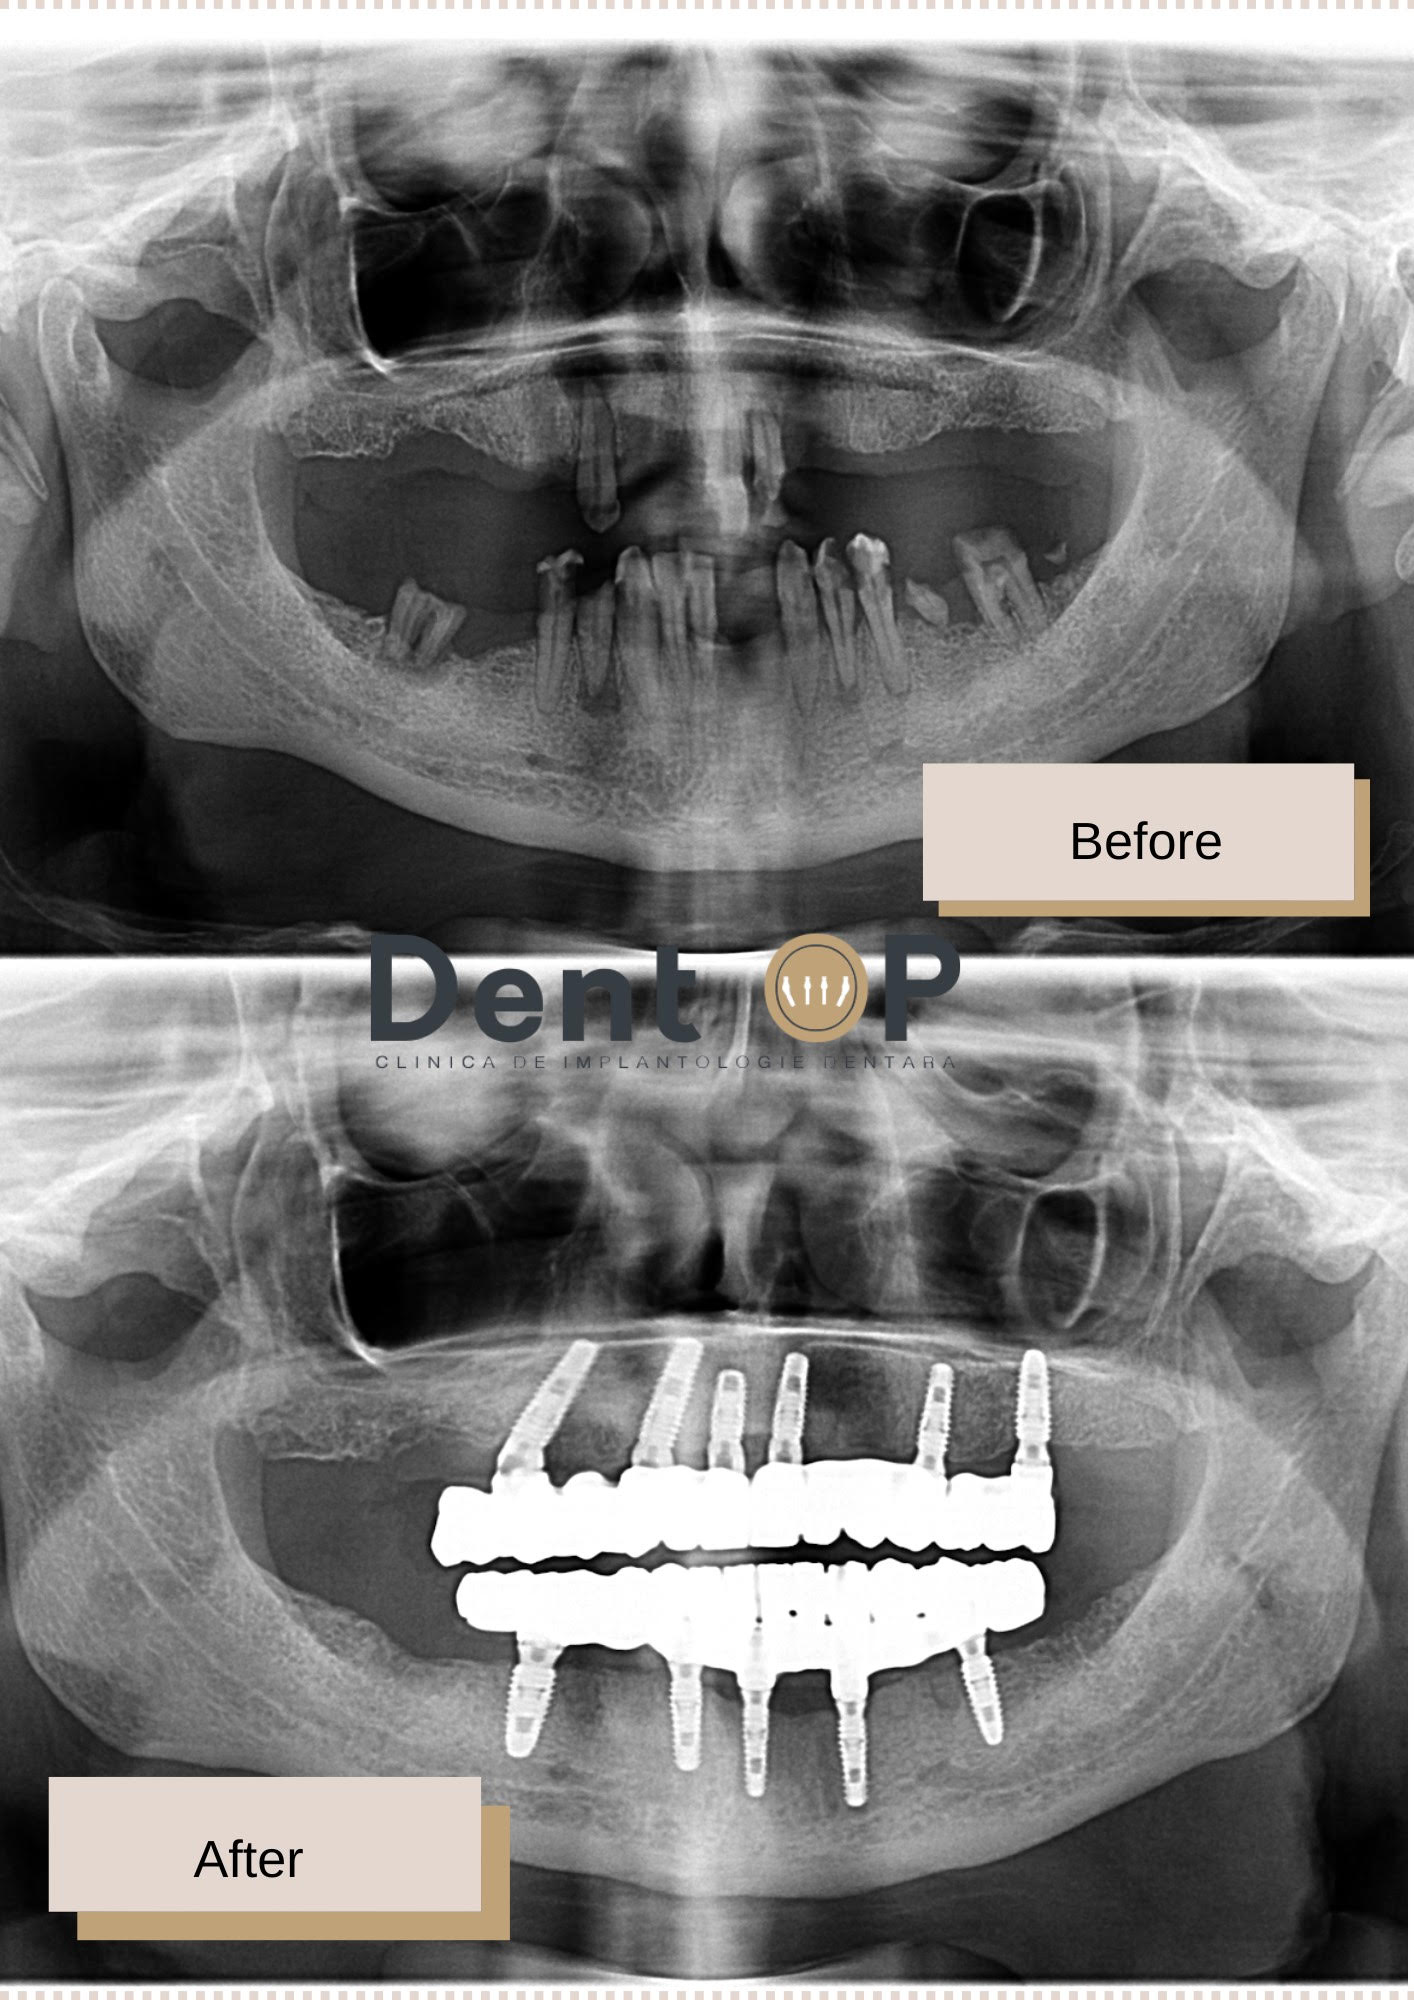

Doamna G. este una dintre pacienții care au trecut printr-o intervenție foarte complexă. Cazul său clinic este impresionant pentru că starea inițială a danturii a fost extrem de afectată. Dinții erau afectați de mai multe carii dentare și traumatisme, dar și de boala parodontală. Un chist a fost văzut pe radiografie încă de la prima consultație cu Dr Cazacu Corrado.

Planul său de tratament a fost urmat în cadrul clinicii noastre și a constat în inserarea a 11 imlanturi dentare, 6 la maxilar și 5 la mandibulă, toate într-o singură ședință cu Sedare Conștientă.

După 6 luni i-au fost inserate și lucrările finale, care sunt spectaculoase așa cum vedem și în imaginile de mai sus.